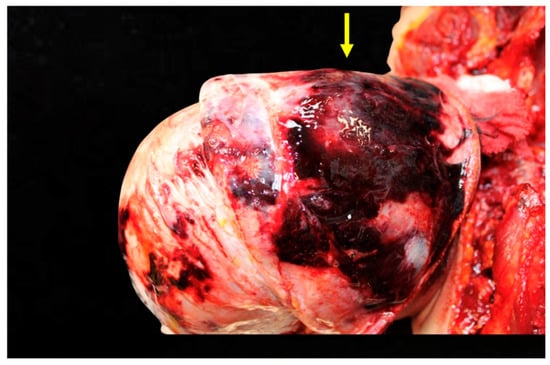

Figure 2. Cerebral hemorrhage found upon opening of the skull. This figure reveals extensive subarachnoid hemorrhage (SAH) visible upon gross examination. The bleeding pattern suggests rupture of vessels in the subarachnoid space, likely due to rapid deceleration forces during the accident.